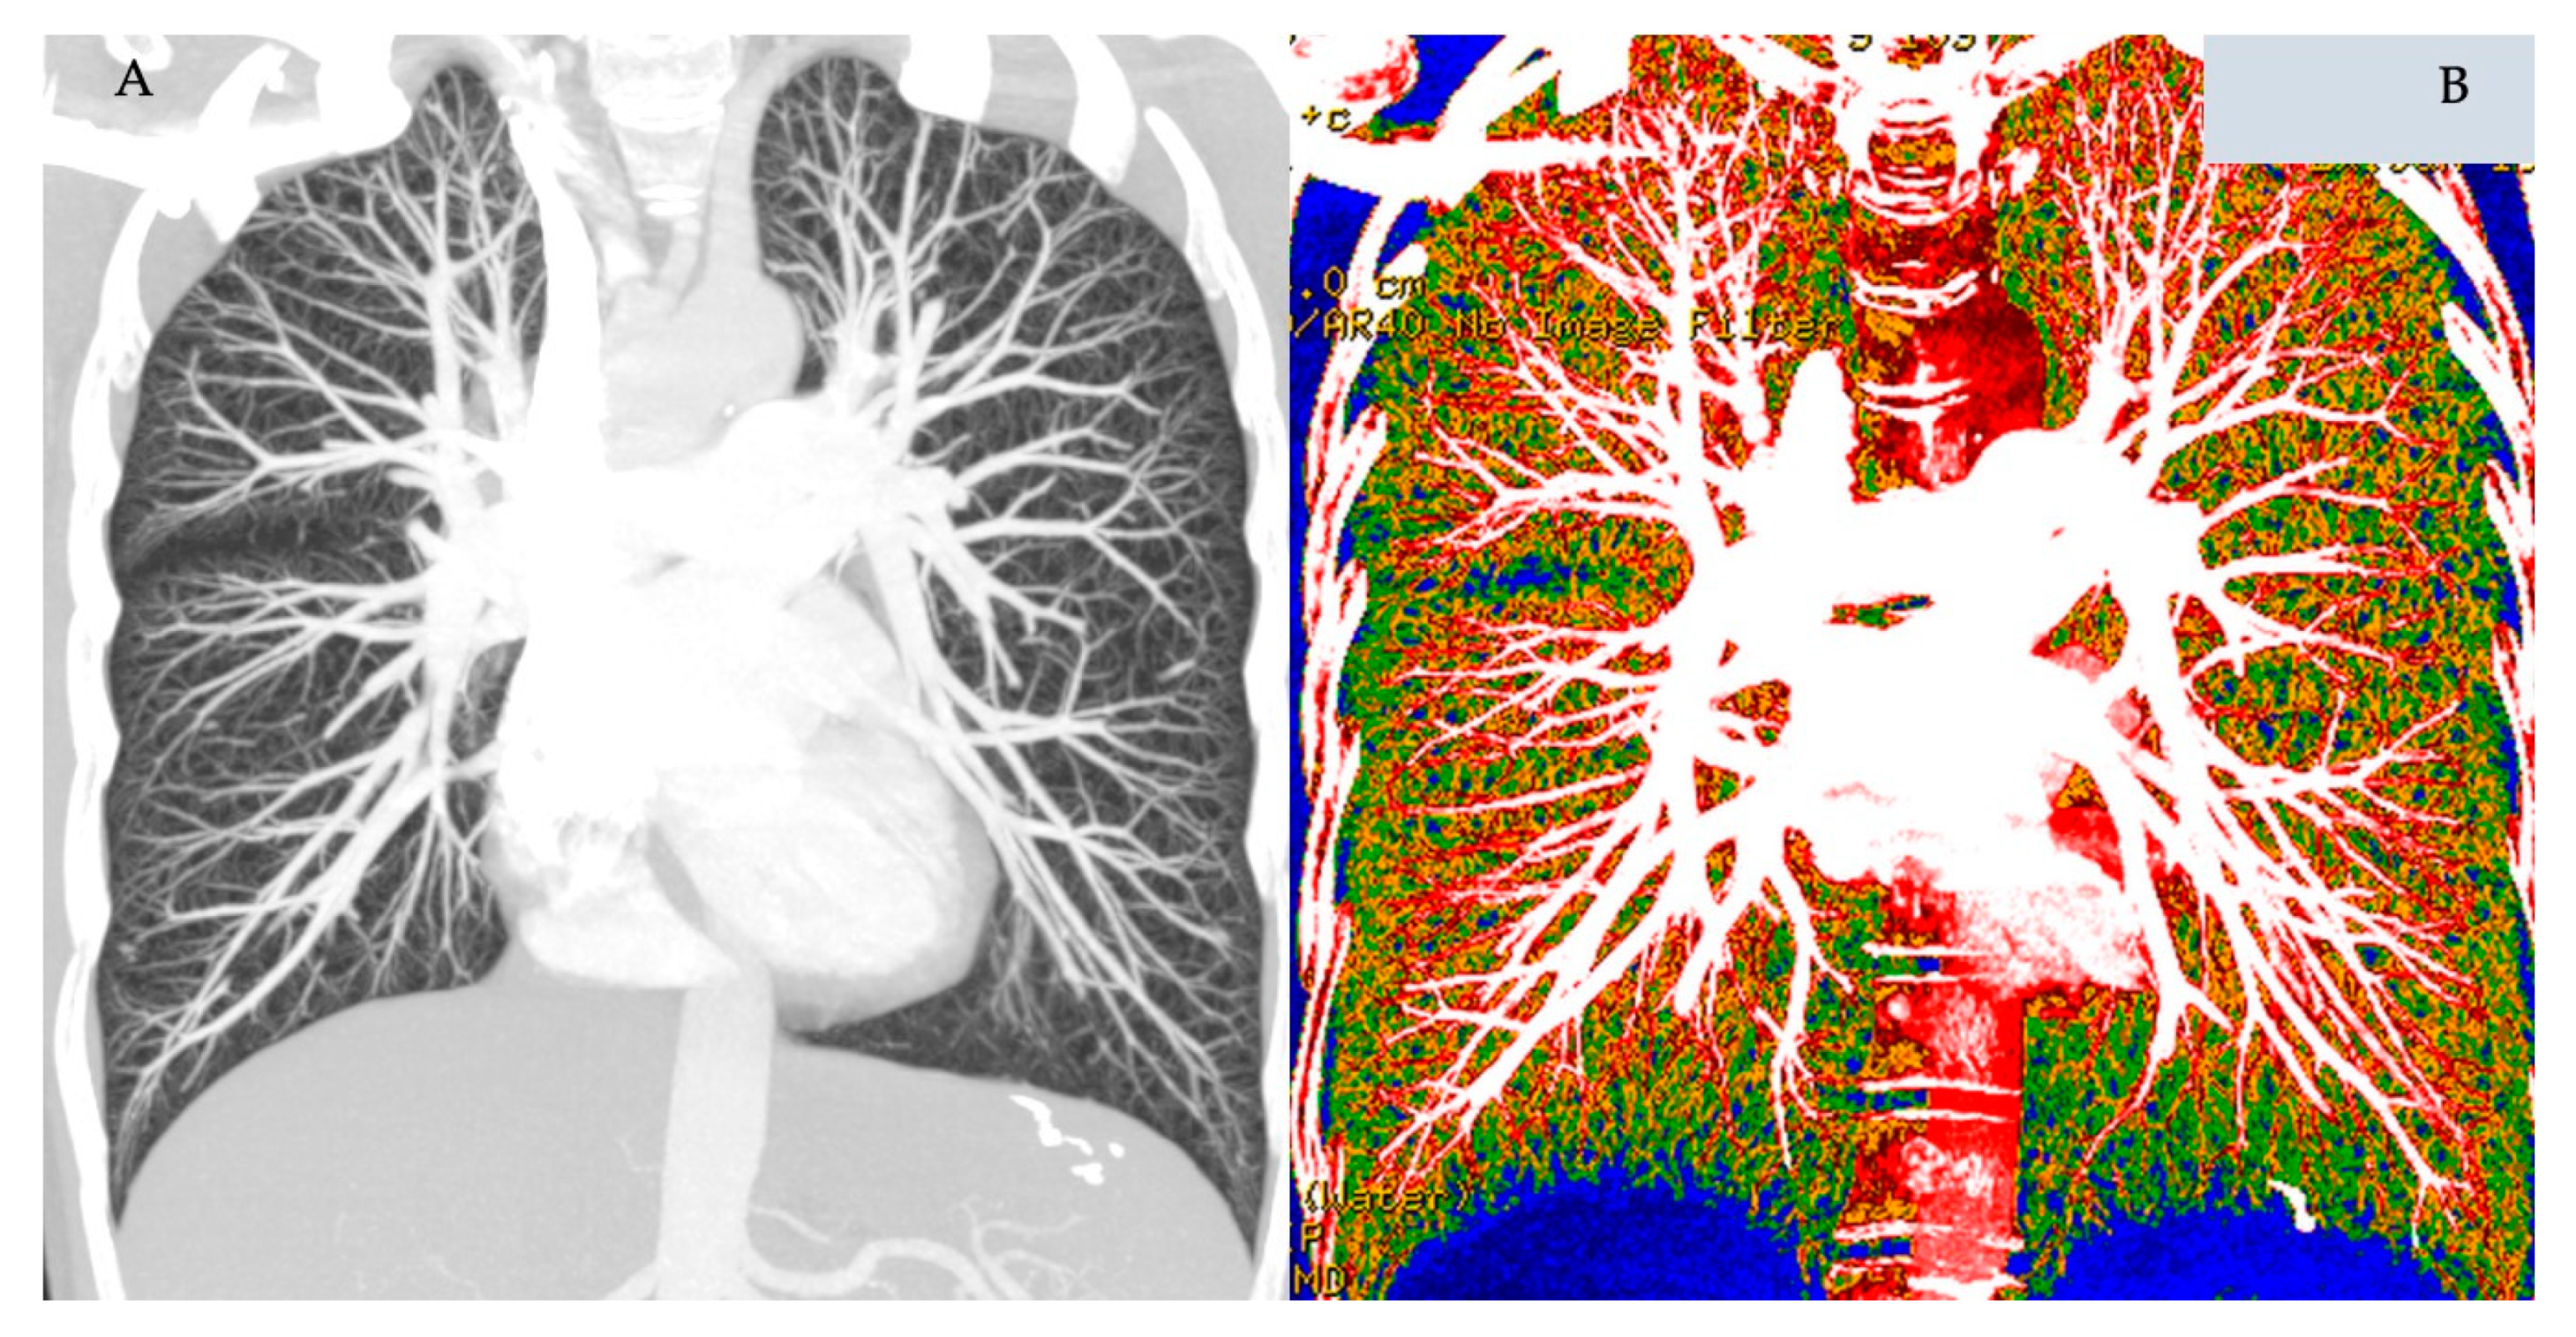

3.2. Dual Energy CT, DECT